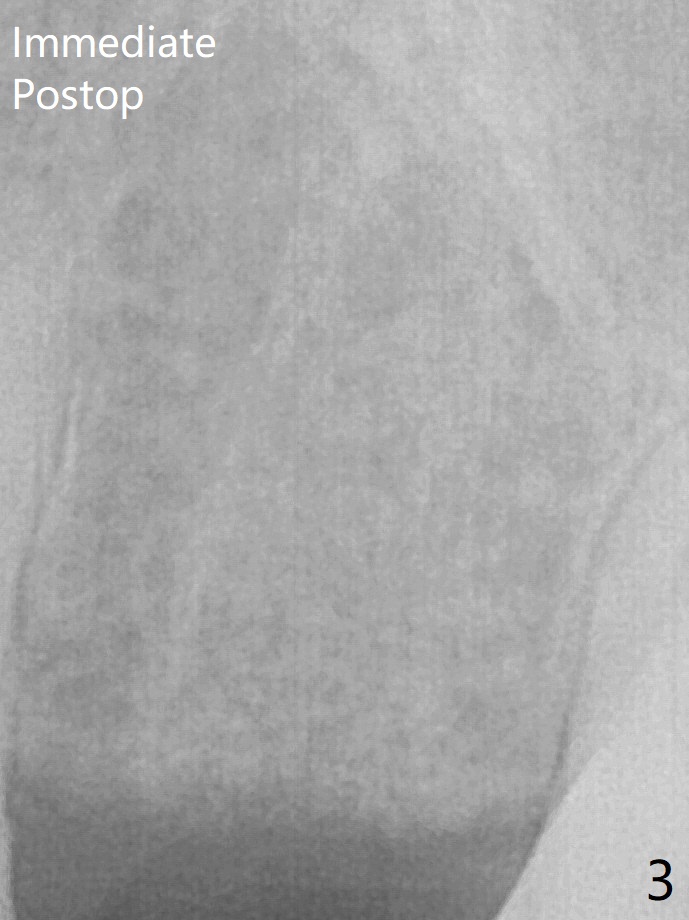

The coronal lamina dura becomes indistinct 5 months postop (Fig.6). The bone graft remains in the socket. There appears no bone graft loss. Great? Ready for implant placement? What is the next step?